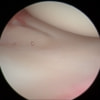

関節鏡検査を実施いたしました。関節鏡検査では、重度の滑膜炎および前十字靭帯の完全断裂が認められました。半月板に損傷は認められませんでした。

関節穿刺を行い、好中球はなく、少数のマクロファージや滑膜細胞が認められるました。膝蓋骨脱臼および前十字靭帯断裂による退行性の関節炎を疑い、関節鏡検査を実施いたしました。関節鏡検査では、重度の滑膜炎および前十字靭帯の完全断裂が認められました。内外側とも半月板に損傷は認められませんでした。